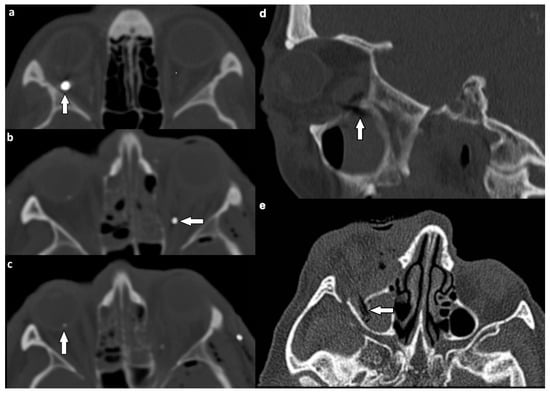

| Location of Soft Tissue Injury | Type of Lesion | n (%) |

|---|---|---|

| Extraocular muscles | 54 (53.5) | |

| dislocation | 45 (44.6) | |

| pierced by bone fragment | 8 (7.9) | |

| intramuscular foreign body | 1 (1.0) | |

| Ocular globe and lens | 38 (37.6) | |

| Deformed globe or vitreous body | 24 (23.8) | |

| rupture of ocular globe | 7 (6.9) | |

| dislocated lens | 6 (5.9) | |

| intraconal foreign body | 1 (1.0) | |

| Optic nerve | 24 (23.8) | |

| elongation | 13 (12.9) | |

| otherwise altered morphology | 10 (9.9) | |

| pierced by foreign body | 1 (1.0) | |

| Orbital vessels | 16 (15.8) | |

| dilated superior ophthalmic vein | 10 (9.9) | |

| direct carotid cavernous fistula | 6 (5.9) |